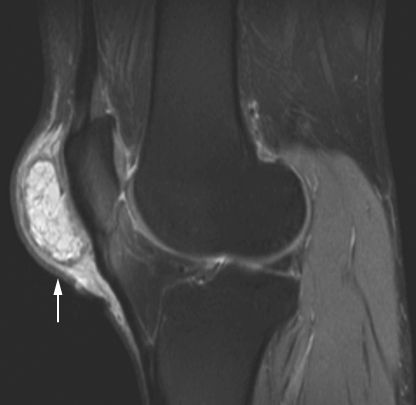

Заболевание сустава: симптомы и лечение